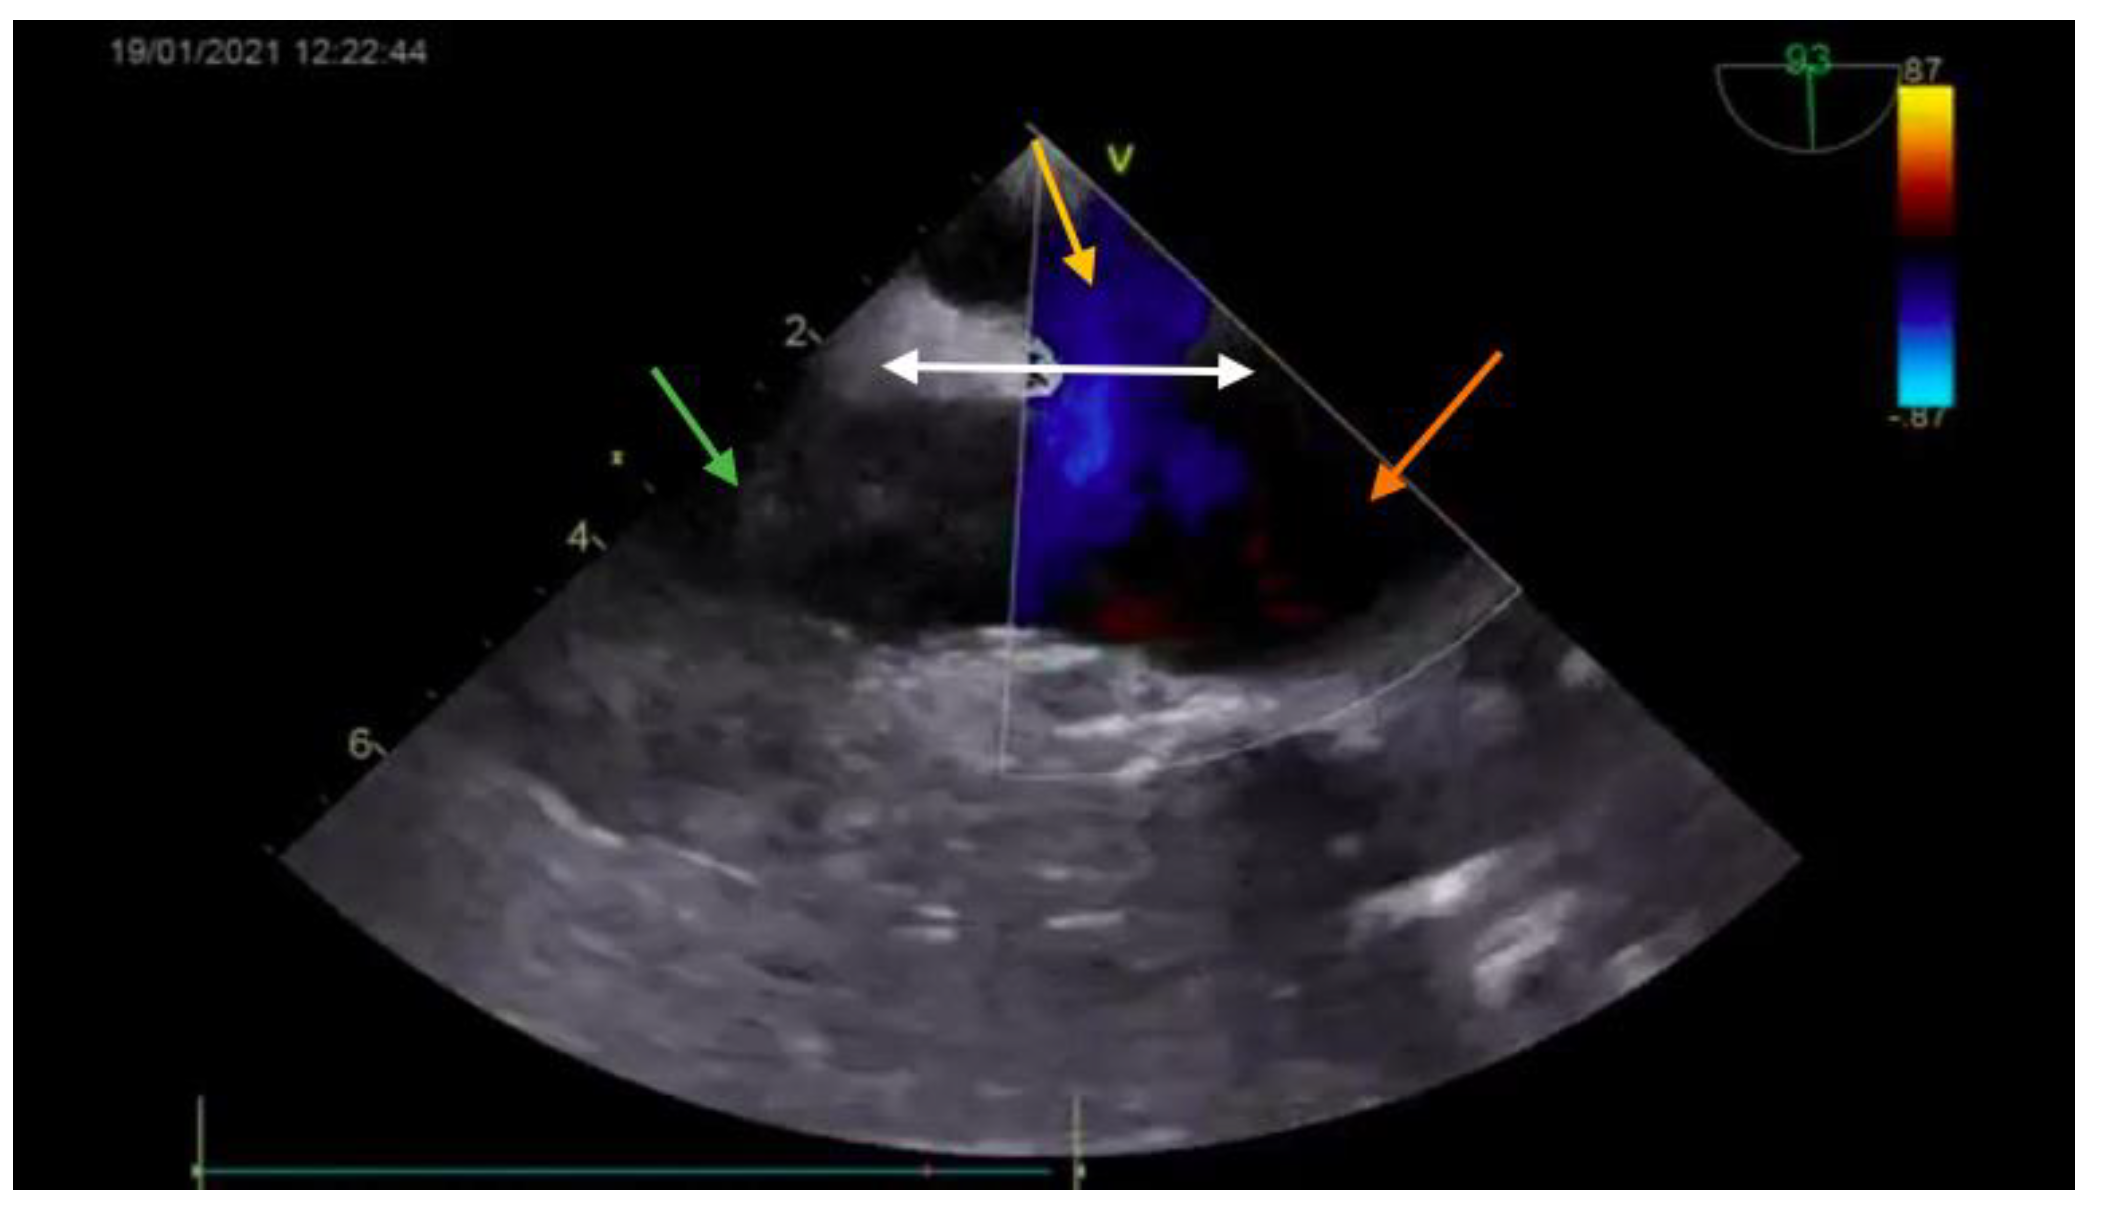

The diagnosis was based on the transthoracic echocardiography (Figure 1 and Figure 2). It revealed an SV-ASD with PAPVD which appeared to open in the right atrium, a dilated right atrium and ventricle, and a left-to-right shunt with Qp:Qs of 2.3 (Qp-pulmonary flow/Qs-systemic flow). The patient had normal pulmonary artery pressure, which was measured during echocardiography.

Figure 1. Preoperative echocardiography (bicaval view—Doppler; SVC—green arrow; right atrium—orange arrow; interatrial septum—white arrow) showing the ASD (yellow arrow).